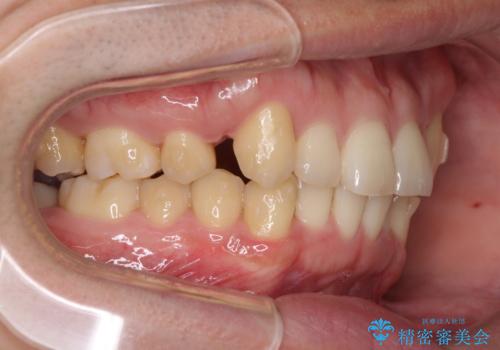

- 上顎の八重歯と前歯のデコボコを気にして来院された患者様です。

八重歯の移動量が多く、インビザライン単体での治療は困難と判断し、補助装置により八重歯移動後にインビザラインを用いることとしました。

上顎のみの抜歯矯正をインビザラインで行う場合、奥歯の前方移動がインビザラインでは苦手のため、奥歯の咬み合わせが不十分となることがあります。

今回の治療では終了時に奥歯は接触しているものの、接触の程度は物足りないものがある状態でした。今後保定期間に少しずつ奥歯の咬合を改善させていくことになります。